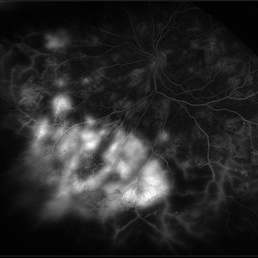

Central Retinal Vein Occlusion with Severe Ischemia

Composite fluorescein angiogram of the left eye of a male with a Central Retinal Vein Occlusion with severe ischemia.

Photographer: Olivia Rainey

Imaging device: Heidelberg Spectralis

Condition/keywords: central retinal vein occlusion (CRVO), composite, fluorescein leakage, ischemic CRVO